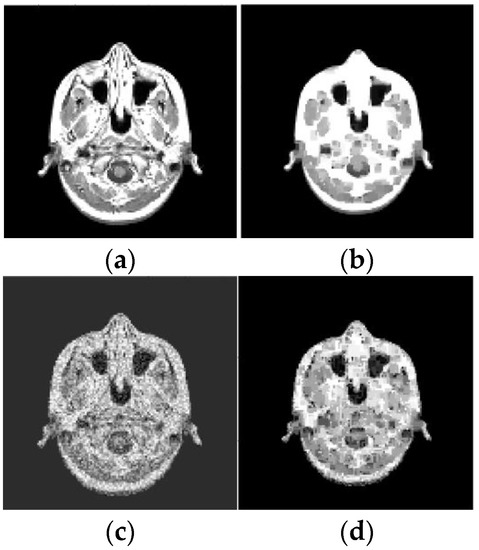

Figure 9.

Results of reconstruction of MRI image based on qualitative data. (a) Original image; (b) Reconstructed image; (c) Original noisy image; (d) Reconstructed noisy image.

As before, the ER data were obtained using pixels squares that were scanned in each of 20 layers, and their scan period was 1 pixel. The SNR, which is defined for an average image intensity, is 9.7 dB (for Figure 9c), 23.3 dB (for Figure 10c), and 9.3 dB (for Figure 10e). Note that Figure 9d and Figure 10d,f also demonstrate the noise reduction ability of the reconstruction algorithm (15), (16), (27).